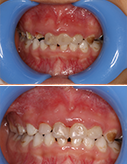

21个月牙套毕业,完美